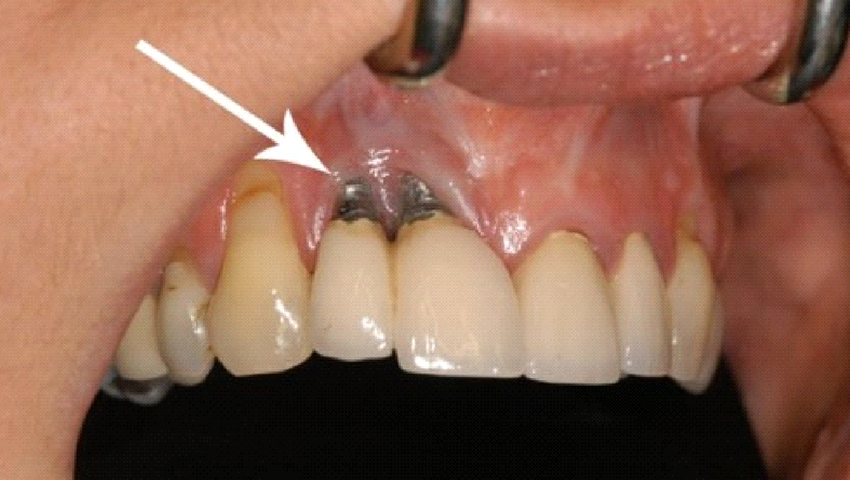

Nhiễm trùng tại vị trí phẫu thuật

Đây là biến chứng mà khách hàng rất dễ gặp nếu như vết thương hở sau khi cấy ghép không được vệ sinh sạch sẽ. Hoặc khách hàng cấy ghép ở môi trường không được vô trùng, vô khuẩn cũng sẽ gây ra tình trạng này.

Trụ Implant bị đào thải

Đào thải trụ Implant là một trong những biến chứng dễ thấy của việc cấy ghép Implant không đạt tiêu chuẩn. Việc trụ Implant không bám chặt vào xương, trụ lỏng lẻo và chỉ cần rút nhẹ là ra. Hậu quả là khách hàng sẽ cần phải cấy ghép một trụ Implant khác.